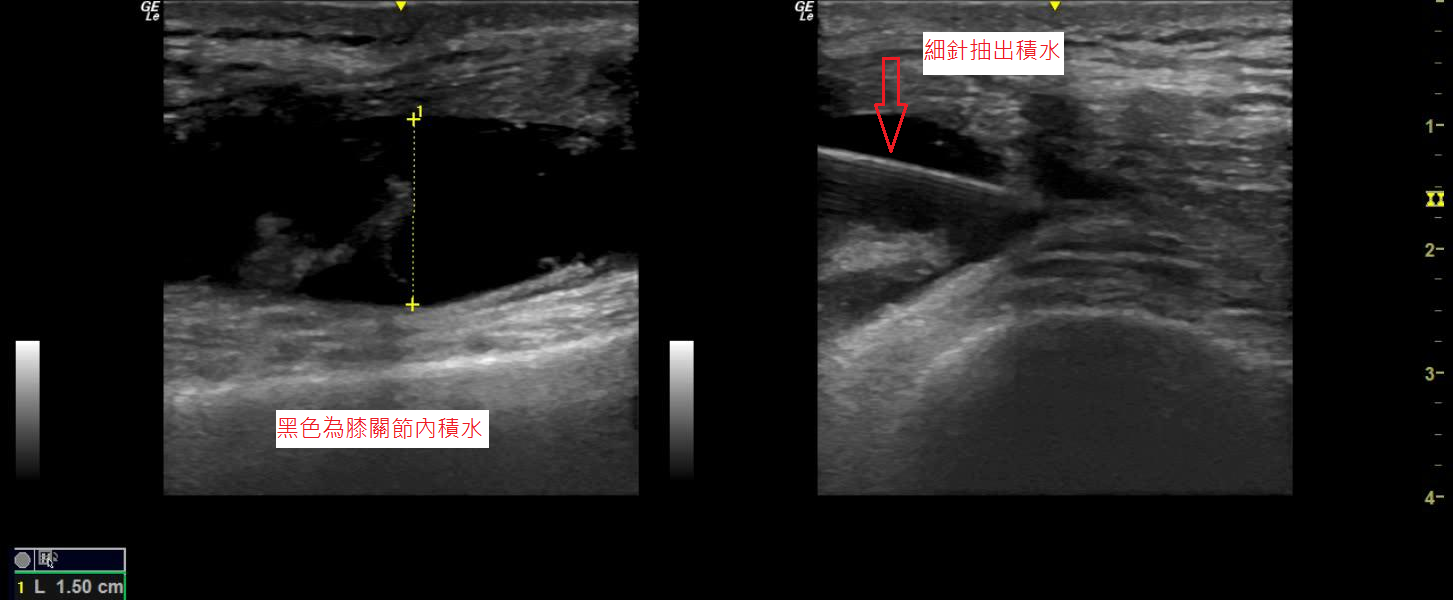

膝痛的患者,超音波下發現膝關節積水,在超音波導引下將積水抽出。

【圖3】膝痛的患者,超音波可以發現膝關節積水及輔助醫師精準治療。